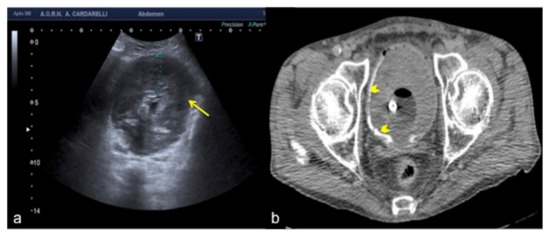

Figure 17. Transverse US image of the left hypochondrium (a) shows a large hypoechoic area misinterpreted as splenic hematoma (arrows) in a 31-year-old woman investigated for trauma. On CT scan (b) it appears to be a gastric fundus distended by fluid (arrows).

Figure 18. Longitudinal US pelvic scan (a) shows a small, triangular, hypoechoic area which may be misinterpreted as free fluid (arrows). On CT scan (b) it appears to be an intestinal loop (arrows).